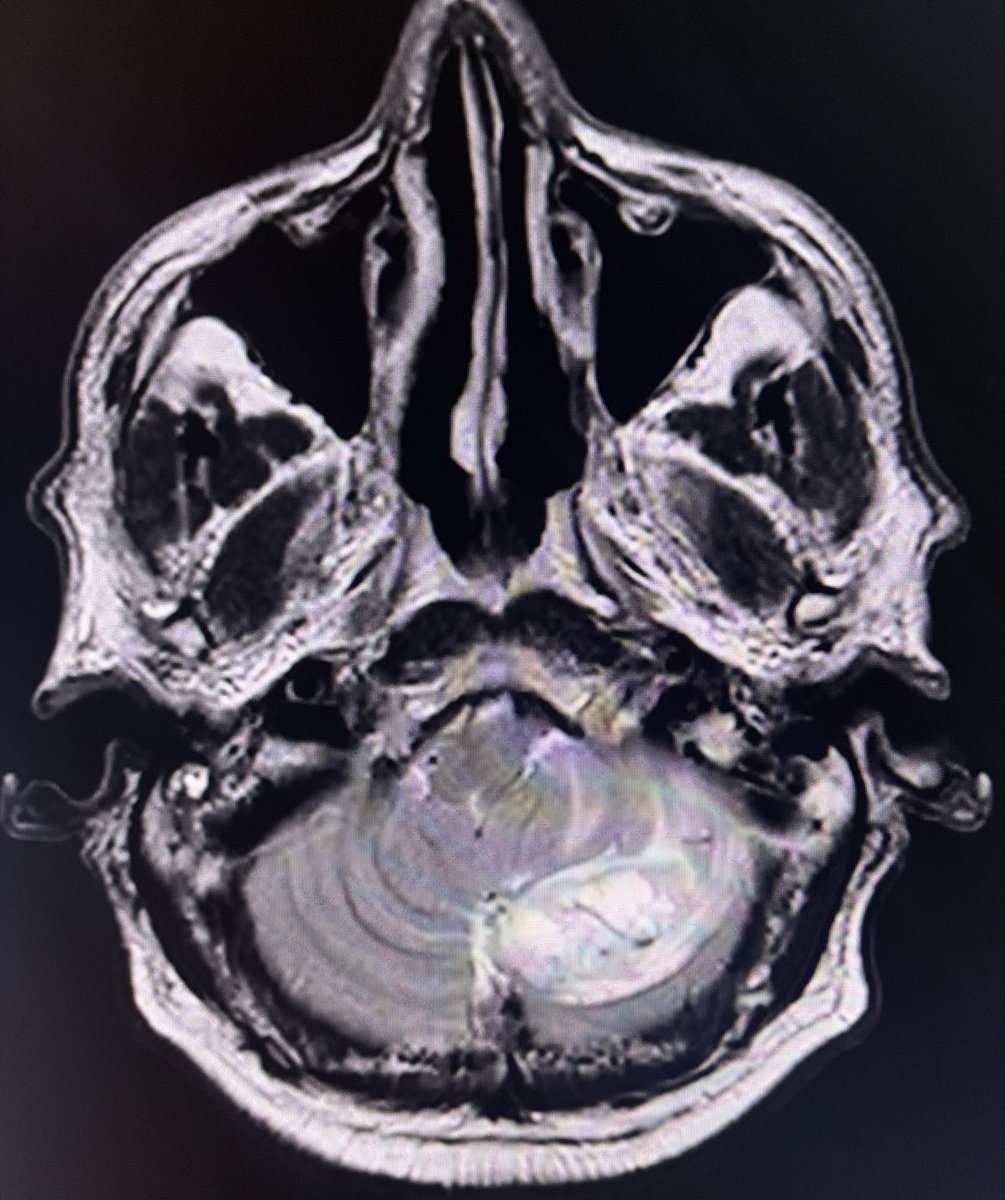

67 year old male with headache.

Contrast images are in 🧵.

This case is a reminder that Age, Gender, location of lesion, They all point to help narrow the differential diagnosis apart from signal characteristics when we report images.

Lesion in left cerebellum - T2 hyperintense lesion, no diff restriction, intense enhancement with feeding vessels also seen on T2 as flow voids - posterior fossa tumour in elderly male - highly in favour of Hemangioblastoma - DD is metastasis.